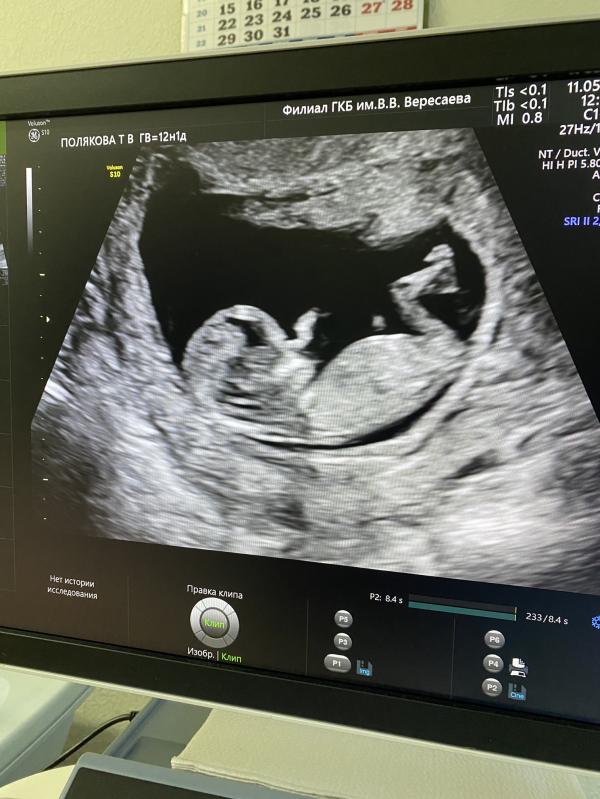

1 скрининг. Часть 1.

11 мая была записана от ЖК в 17 роддом на 1 скрининг, попала я к врачу фамилия на букву Т.. не запомнила, 230 кабинет.

Долго смотрела и сына не хотел поворачиваться личиком. Убегал прям от датчика. Отправила она погулять, тип повернуться должен.

Обратно захожу в кабинет, смотрит , вроде повернулся, но все равно не полностью и в итоге говорит: на НИПТ отправлю, нос не вижу. Но вы не переживайте, одевайтесь.